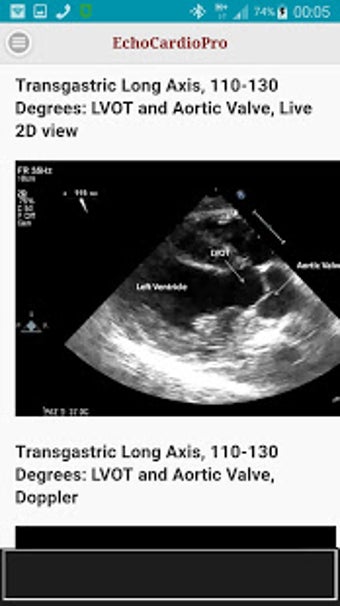

Aplikacja dostarcza kompleksowych informacji na temat echokardiografii przezklatkowej (TTE) i echokardiografii przełykowej (TEE) oraz ich odpowiednich korzyści w ocenie czynności skurczowej i rozkurczowej lewej i prawej komory, regionalnego ruchu ściany, wad zastawkowych serca i chorób osierdzia. Zawiera również szczegółowe informacje na temat różnych widoków, takich jak długoosiowy przysercowy, krótkoosiowy przysercowy, wierzchołkowy, podżebrowy, nadobojczykowy, śródprzełykowy, poprzezżołądkowy, głęboko poprzezżołądkowy i wysoko przełykowy.